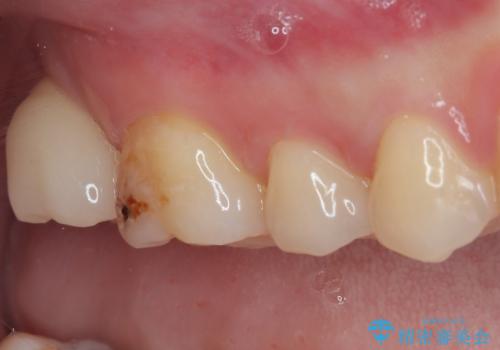

- 過去の歯医者通いの恐怖から虫歯を放置してきたものの、一大決心して来院された患者様です。

神経組織の失活している歯や歯根だけが残っている歯などがあり、全体的に歯石も多く付着している状態でした。

まずは歯石除去とブラッシング方法などの衛生指導を徹底的に行って口腔内環境を改善し、汚れの溜まりやすくなっている親知らずは全て抜去することとしました。

その後、歯根だけとなっている歯はインプラントに、神経組織の失活している歯は根管治療を行い、いずれもオールセラミッククラウンにて補綴治療を行うこととしました。

右上のインプラント治療は、1DAYインプラント治療(抜歯即時埋入・即時荷重)の適応となりましたので、通常3回必要な外科処置の回数を1回に集約させることができました。